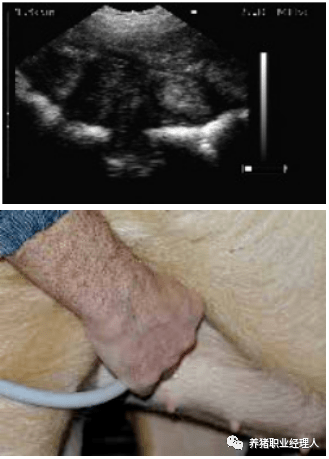

扫描仪的探头涂上耦合剂后置于腹股沟部。

缓慢地移动探头,直至出现胚胎清晰的图像。

如果图像模糊不清,需要涂更多的耦合剂。

位置1的超声波图像.

位置2的超声波图像.

位置3的超声波图像.

位置4的超声波图像.

位置5的超声波图像.